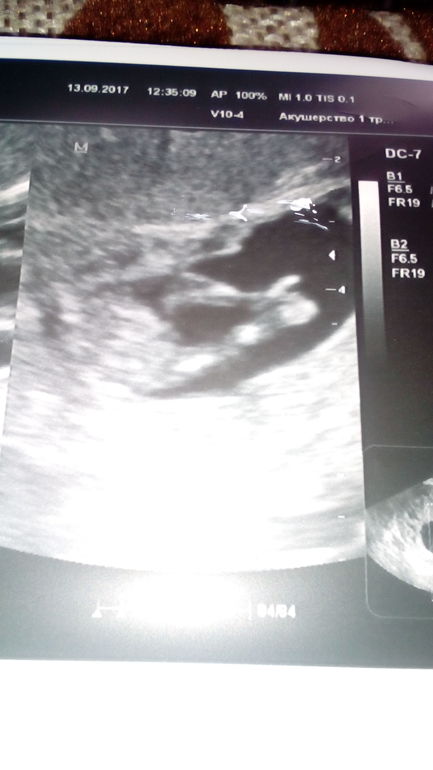

На УЗИ малыш толи нос чесал,толи ручки так сложил,на лице короче они у него были,да и ещё мне врач сказал"Мол,не буду утверждать, но явно вижу мальчика", я чуть с кушетки не упала...

.гляньте может действительно,а может потом мальчик будет девочкой?рановато ведь ещё...

а вот наша фигулька,что скажете?